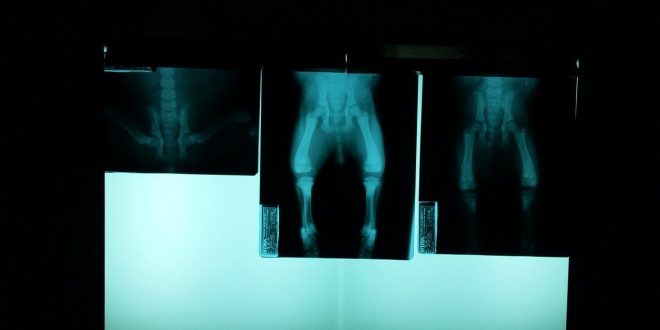

En primera instancia, y después de hacerle radiografías, los médicos advirtieron que el niño de 12 años tenía entre 25 y 30 imanes; sin embargo, después de una operación de seis horas, se confirmó la presencia de 54 objetos metálicos.